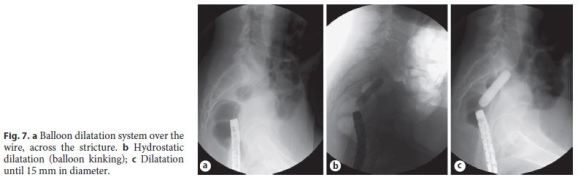

The patient was then medicated with Goserelin, a luteinizing hormone-releasing hormone analogue (3 administrations of 3.6 mg, with a 28-day interval between each dose, given subcutaneously). After medical therapy, a pelvic MRI documented favorable evolution, with reduction of the foci of endometriosis and frankreduction of the signal, translating evolution to fibrosis (Fig. 6). The endoscopic reassessment revealed a larger stenotic caliber, but still impassable with the adult colonoscope. Endoscopic dilatation (5 sessions with through-the-scope balloon up to 15 mm) was successfully performed (Fig. 7).

Colonic resections in this setting improve quality of life but can result in different complications, including anastomotic strictures (AS) [15], as seen in this case. The incidence of AS after colorectal surgery for endometriosis has been found to range between 2 and 5% [1618], but in a recent series of 113 colonic resections there was a rate of 12%, a higher incidence than for other indications than endometriosis. The etiology of AS is rarely known and seems to be multifactorial [19]. Several endoscopic dilatation techniques can be used [20] to treat AS. Generally, pneumatic dilatations are preferred due to its lower risk of mucosal laceration and perforation. With balloon dilatations, 24 procedures are often needed. The procedure is usually well tolerated and has an efficacy of 90% [19]. Our patient experienced AS after surgery, which was successfully treated with 5 sessions of balloon dilatation.